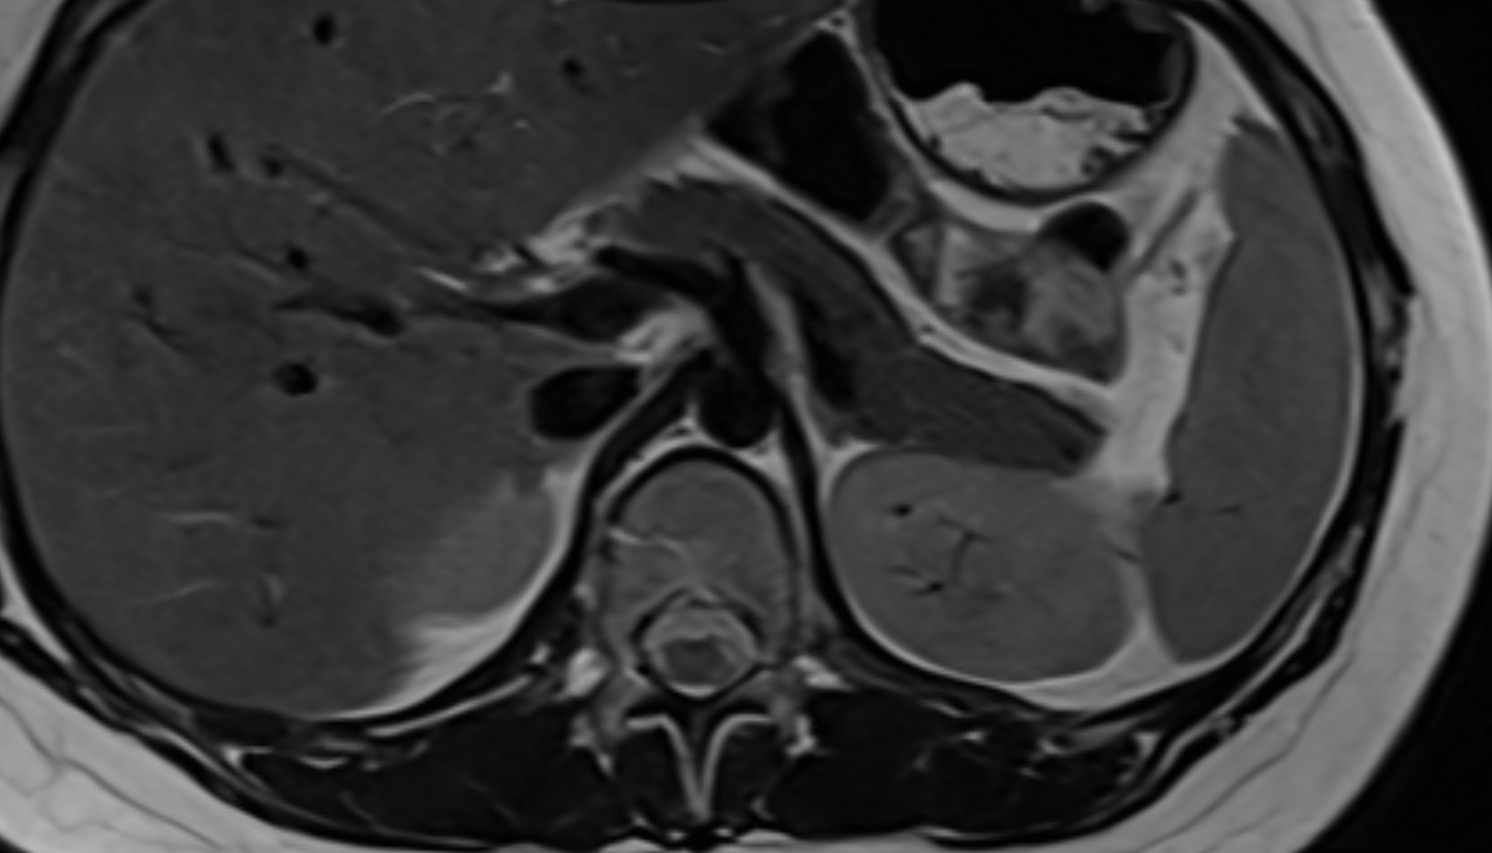

- kidneys

- Right kidney

- Left kidney

- Kidney cortex (Renal cortex)

- Renal capsule

- Renal medulla

- Renal pyramids